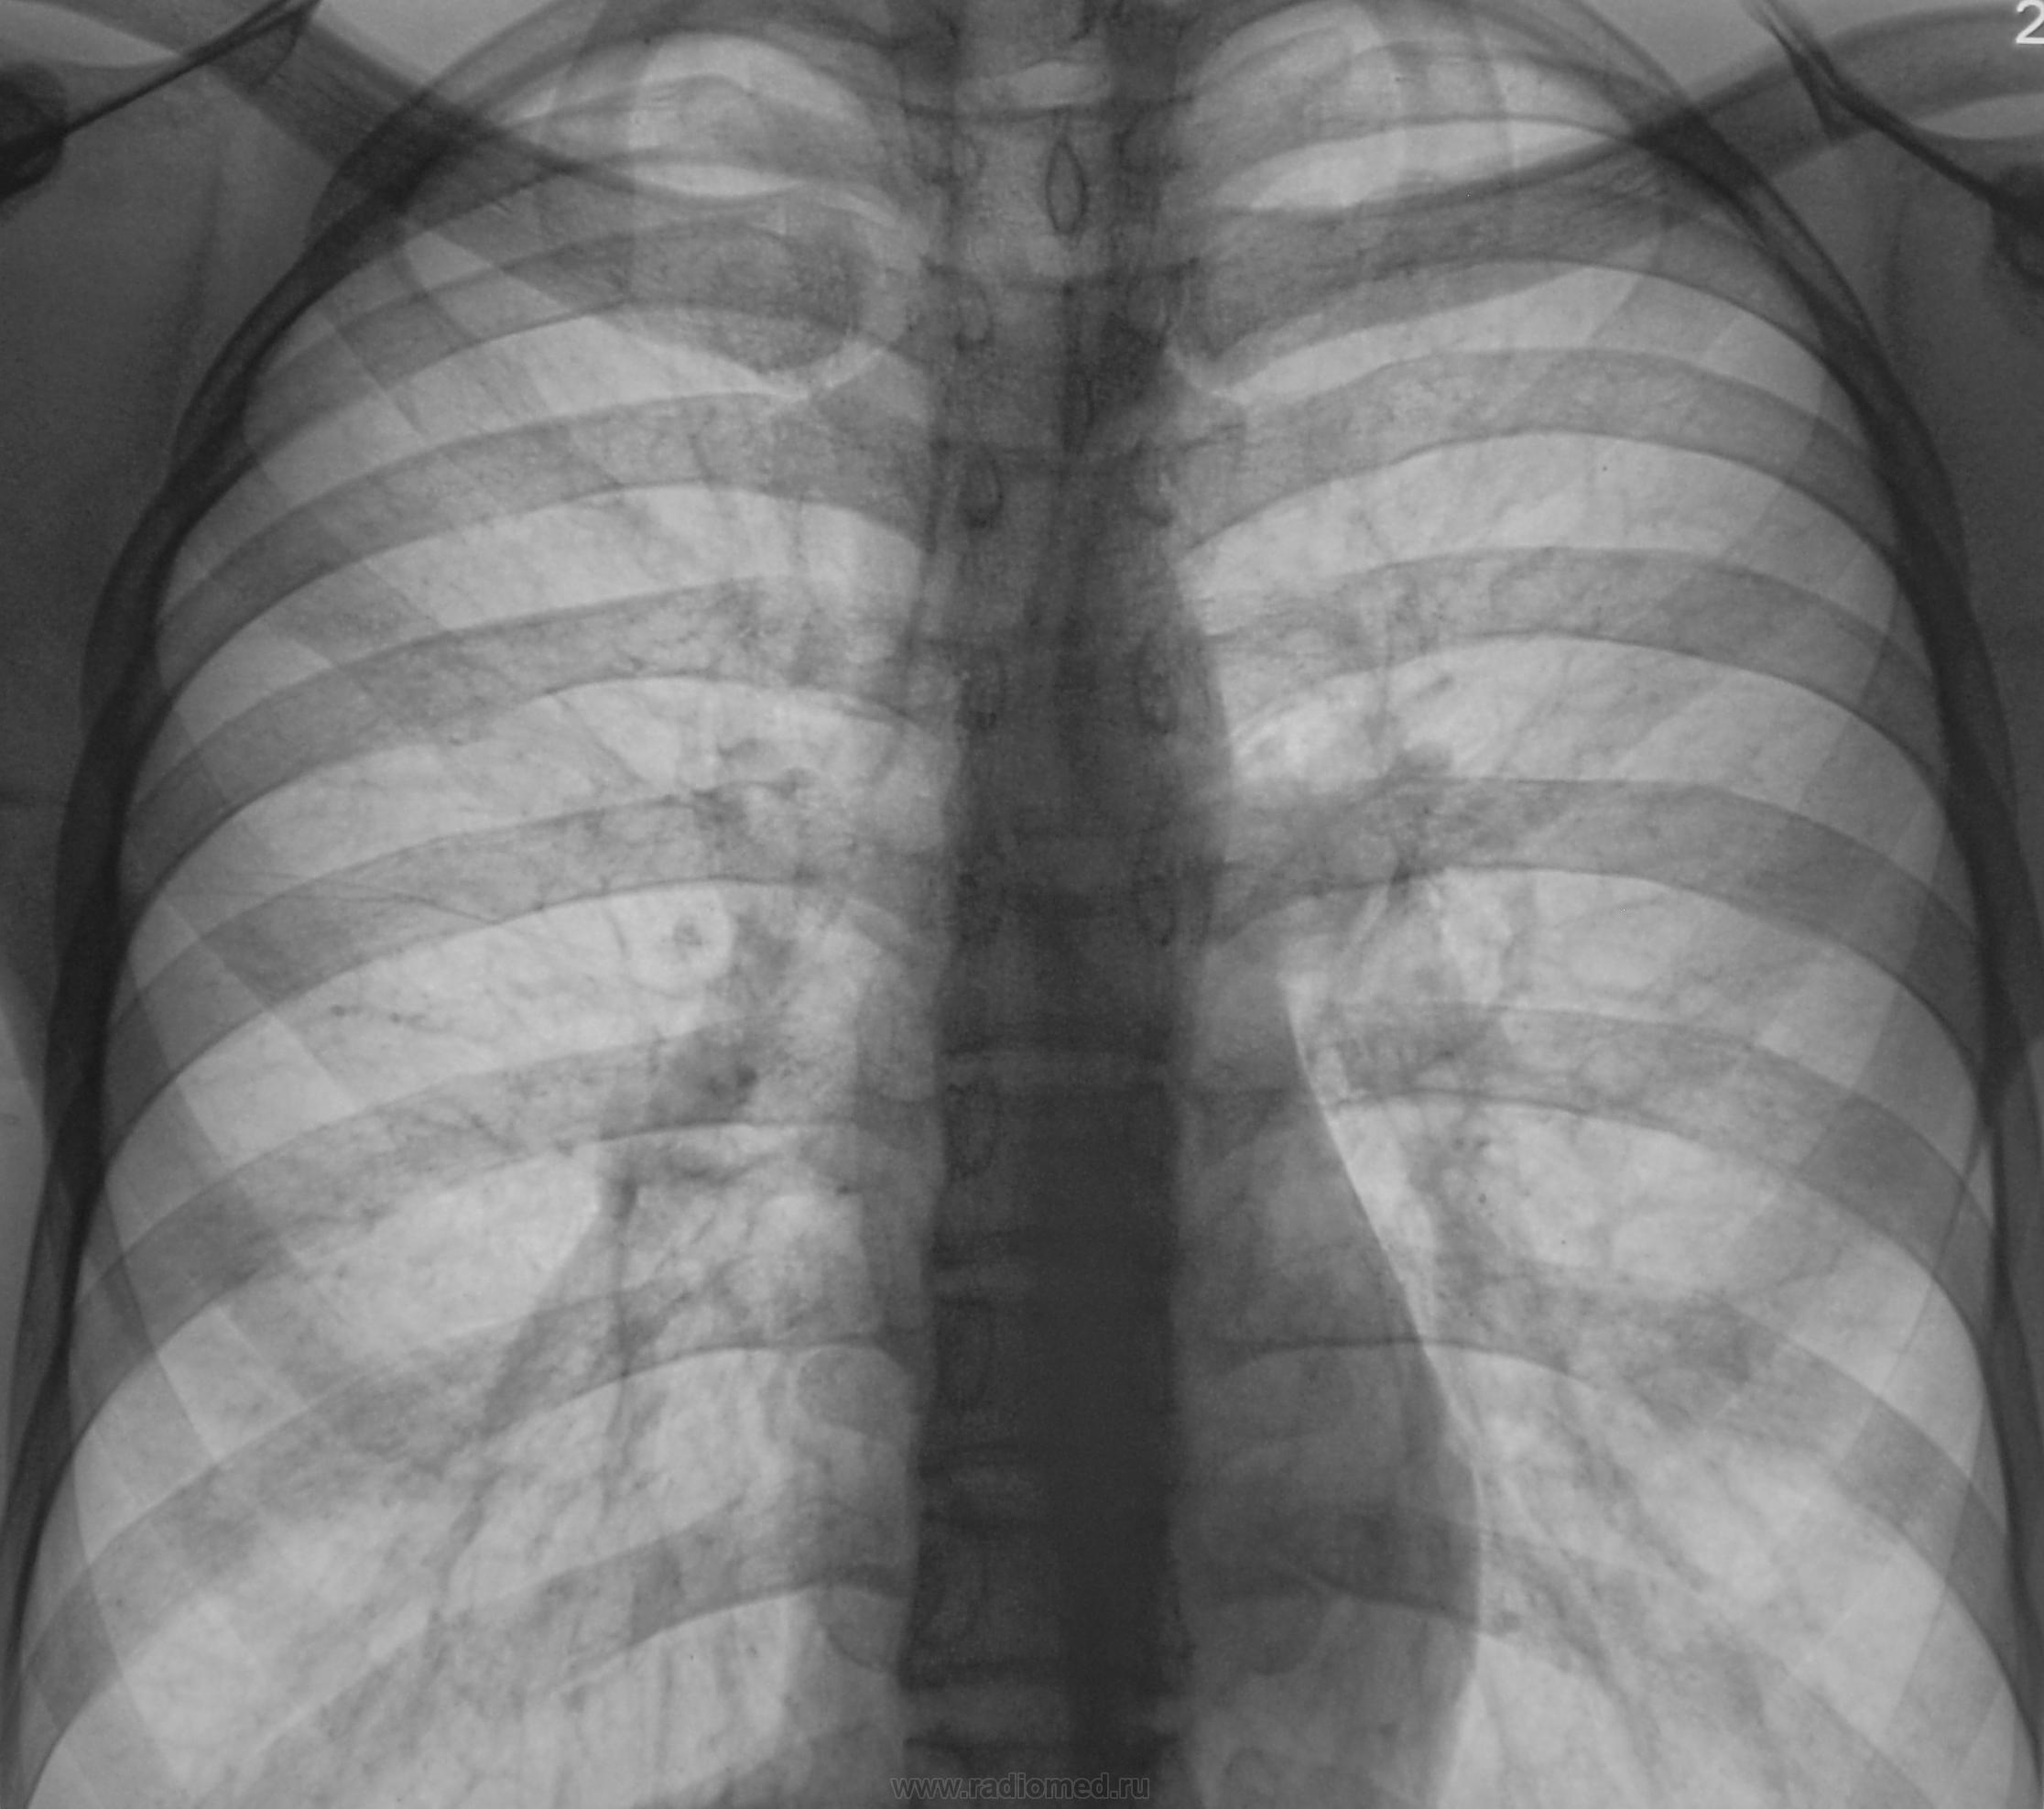

Пациент взят на контроль после флюорографии. Произвели только обзорный снимок.

Прошло 3 месяца, и сегодня, фтизиатр прислал на «контроль», взятого на заметку.

Стало ясно, что линейная томография в данном случае не повредит.

Какое мнение будет после томографии у уважаемых коллег?